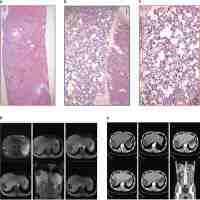

| Abstract | Hepatic angiosarcoma is a rare condition that has been associated with exposure to colloidal solutions of thorium dioxide, vinyl chloride, arsenic and radiation. Therapeutic guidelines have not been definitively established due to the small number of cases of this disease. The present study reviewed 28 cases of hepatic angiosarcoma from studies that had been published between January 2000 and December 2012, in addition to 6 cases diagnosed at Tri-Service General Hospital (Taipei, Taiwan). Clinical staging was based on American Joint Committee on Cancer staging system for soft tissue sarcoma (2014). With a mean follow-up of 27.5 months (range, 0.27–102 months), 18% (6/34) of the patients survived. The 1-, 3- and 5-year survival rates were 68.0±9.3, 42.1±10.2 and 32.7±9.8% for patients with stage I disease (mean follow-up, 32.7 months), whilst the 1- and 3-year survival rates were 33.3±15.7 and 22.2±13.9% for patients with stage IV disease (mean follow-up, 13.0 months). Determining an appropriate therapeutic strategy for this patient group is necessary. New studies encompassing larger patient populations are required in order to analyze and define standard prognostic parameters and to standardize a treatment approach for this extremely rare neoplasm. |